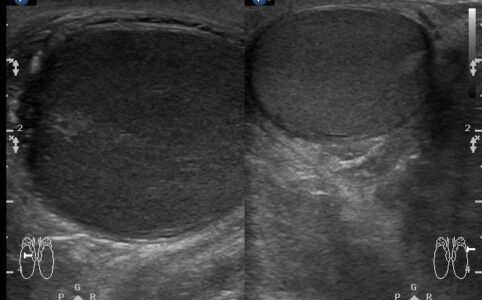

根據這段影像組合,看出那些超音波發現 ?最可能超音波診斷為何 ? 這是2015年的個案,右側睪丸腫痛。我們先看...